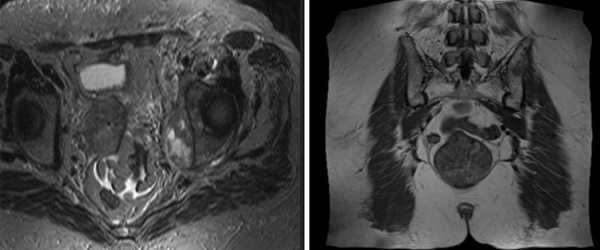

МРТ костей таза показывает множественные очаги, что говорит о метастатическом поражении

МРТ крестцово-подвздошных суставов - типичный воспалительный сакроилеит при аксиальном спондилоартрите (стрелки)

МРТ: двусторонний склероз подвздошной кости с сужением суставной щели (стрелка)